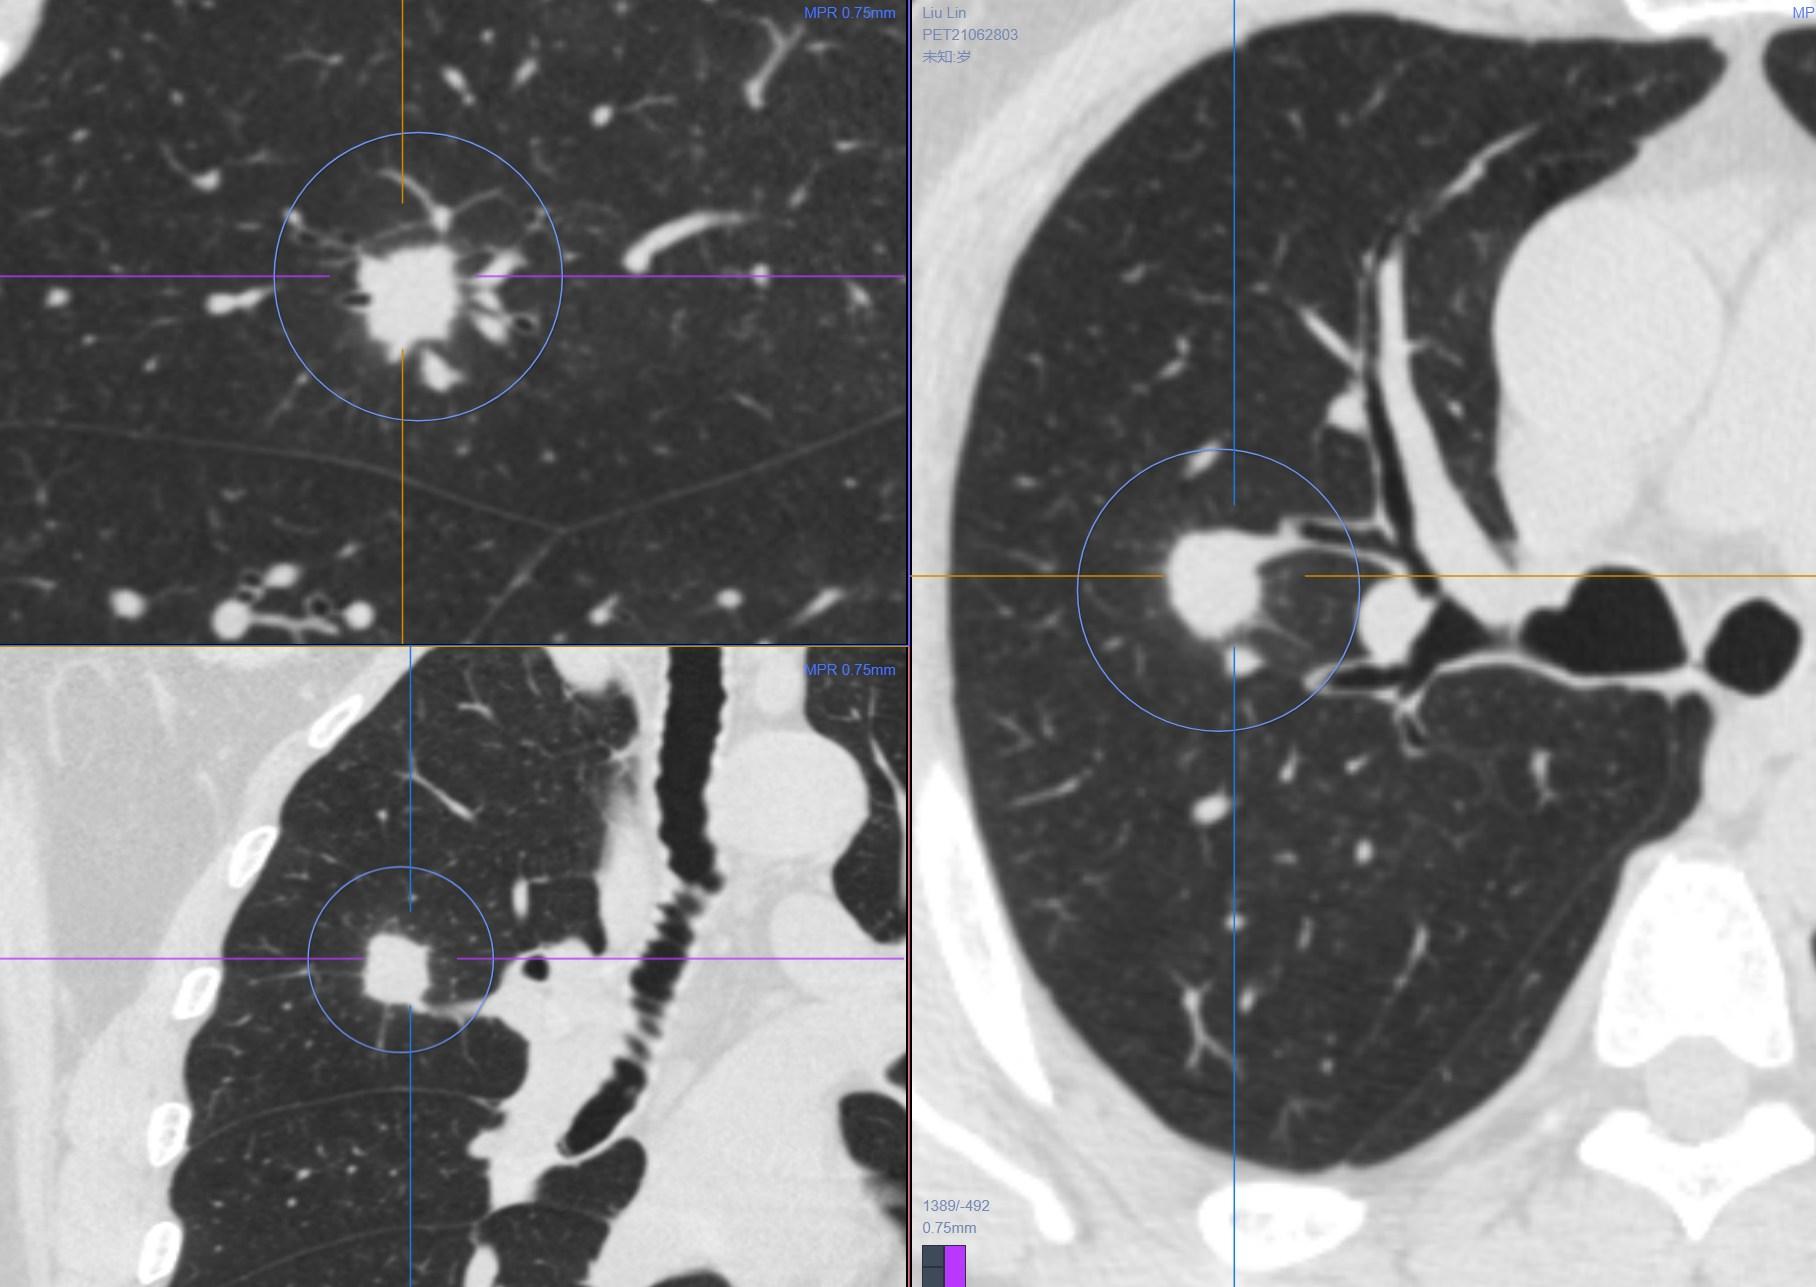

2.女性 56岁 体检发现右肺上叶前段占位,无特殊不适。

啥也不说了,实性软组织结节,大小约1.9cm×1.5cm,和病例1一样,该有的征象都有了……而且还出现支气管的截断、鼠尾征这些典型的特点。但是有没有不太符合的,我们在诊断的时候还是留了一手,建议活检除外感染性病变。